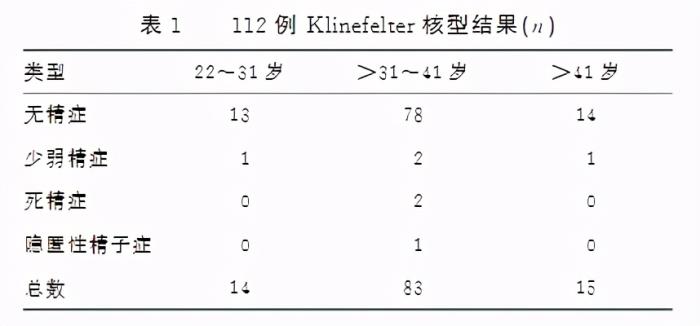

据《检验医学与临床》发布的一项研究显示

克氏综合征会严重影响男性的生育功能

参与研究的这112名克氏综合征男性

他们绝大多数都患上了无精症

因此

如果怀疑自己有上述这些特征

最好及早到医院的男科或泌尿外科

作进一步检查,再下判断

[1]马刚,许超.克氏综合征的生育相关研究进展.山东大学学报:医学版,2019,57(10):67-73.

[2]林俊伟,蔡小华,章钧,侯红瑛.112例克氏综合征患者精液分析.检验医学与临床,2020,17(S01):69-71.